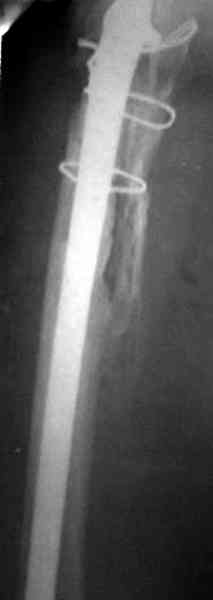

Для спейсера в бедро использовал старый длинный бедренний компонент меньшего диаметра, облепленный со всех сторон цементом с антибиотиком.

Наглухо ушитая рана с дренажом зажила первично, после чего с больной потерял контакт, и только недавно, через 8 лет я осмотрел её. Она без проблем нагружает на конечность и передвигается с помощью трости. От окончательной операции по реконструкции отказывается, довольная результатом.

Имеются литературные данные, когда спейсер держали не более 6 месяцев, но этот случай бьет все рекорды, может быть для наших людей, обременных финансовыми трудностями, нужна другая шкала оценки сроков нахождения спейсеров.

№3-6 снимки с осложнением

и последние снимки.